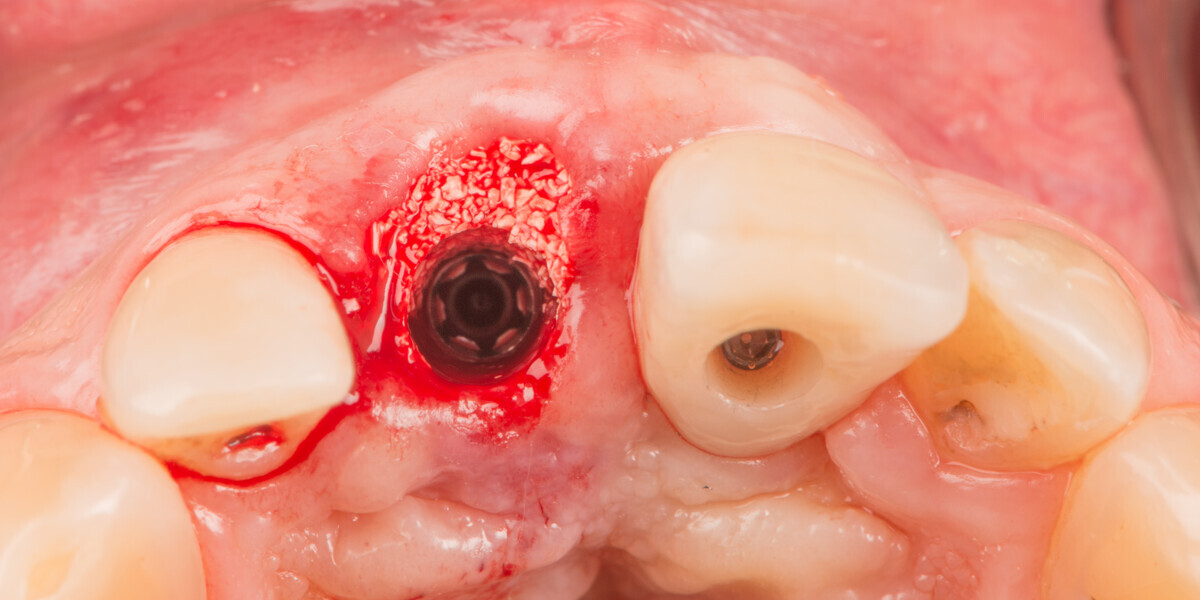

Immediate placement and restoration of a Straumann BLX implant replacing maxillary incisors